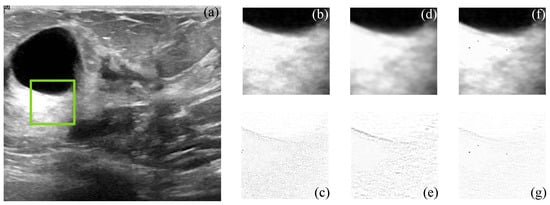

Figure 5. Subjective visual results of the despeckled simulated US image US-sim-04. (a) Input image. Details are taken from the region marked in green: BM3D: (b) despeckled image, PSNR = 15.47 dB, EPI = 0.2791; (c) error image. SD-BM3D: (d) despeckled image, PSNR = 16.07 dB, EPI = 0.2898; (e) error image. CMI-3DSVD: (f) despeckled image, PSNR = 16.35 dB, EPI = 0.3156; (g) error image.

Figure 5 and Figure 6 show the simulated and filtered ultrasound images, indicated as US-sim-04 and US-sim-11, respectively, with the subjective visual comparison with the BM3D and SD-BM3D.

The visual results in Figure 5 and Figure 6 show that the designed framework can achieve good performance for the despeckling procedure. As can be observed, the BM3D technique produces artifacts that degrade the processed images, and the SD-BM3D method tends to over-smooth edges and fine details by comparing the error images. The principal disadvantage of these techniques is that they do not consider the images’ local statistical properties and texture features for grouping the 3D blocks, which limits the denoising performance. The proposed CMI-3DSVD filter outperforms the mentioned denoising methods by preserving important details of the image, such as edges, and by not blurring homogeneous regions.